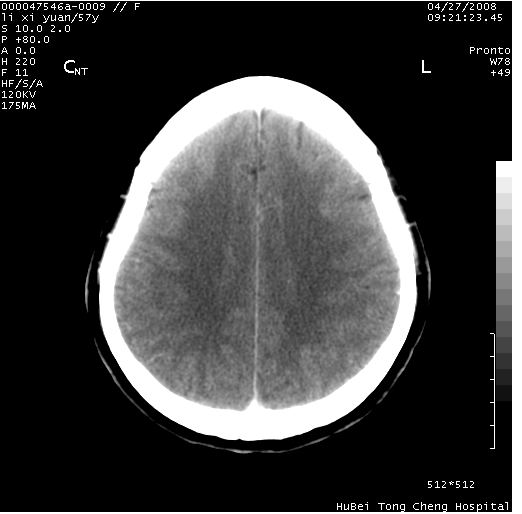

以下是引用余辉在2008-4-27 14:02:00的发言:[br]病灶位于中央沟前方?位于额叶?高密度灶,灶周水肿不明显,病灶似沿脑沟走行,强化明显,局部层面呈现环状强化,考虑1脑表面血管性疾病,如血管瘤,血管扩张,灶内血栓形成,其次考虑肿瘤如脑膜瘤、转移瘤,胶母等

以下是引用形影不离在2008-4-27 14:13:00的发言:[br]考虑胶质瘤可能性大,不排除慢性炎性肉芽肿。建议mri检查。